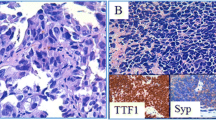

Among MPA cases, 36 patients fell into stage I, 11 into stage II, 6 into stage III, and 2 into stage IV. In LA, 39 (16 solid, 16 acinar, and 7 lepidic) fell into stage I, 12 (10 solid, 1 acinar, and 1 lepidic) into stage II, 8 (4 solid, 1 acinar, and 3 lepidic) into stage III, and 17 (13 solid and 4 lepidic) into stage IV. Seventy-two people had no smoking history, and fifty-nine were smokers, including former smokers and current smokers. The histological images of MPA and LA are presented in Fig. 1.

Immunohistochemical staining and mutation analysis of MPA and LA patients. Three micrometers FFPE sections of MPA (patient 1) and LA (patient 16) were immunostained with hematoxylin and eosin (× 100 magnification). Scale bar 20 μm. Abbreviations: MPA, micropapillary lung adenocarcinoma; LA, lung adenocarcinoma without micropapillary component